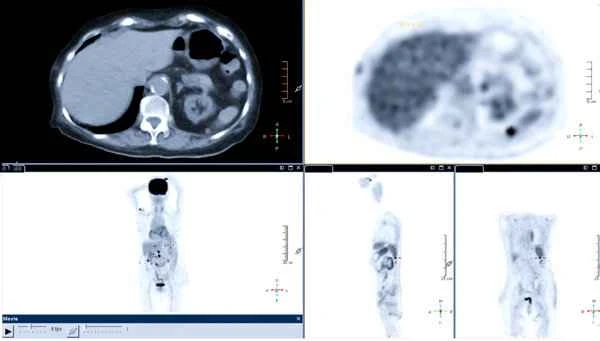

Postoperative scar formation after spleen surgery is a complex physiological process. Following surgery, the tissues in the spleen region undergo a series of changes, including inflammatory responses, cell proliferation, and collagen deposition. These changes ultimately lead to scar tissue formation. Scar tissue is typically harder than normal tissue and has a different color, making it easily identifiable during physical examinations or imaging studies.

When doctors describe a spleen surgery scar, they focus on its size, shape, color, and texture. This information helps assess the scar's healing progress and determine the risk of infection, bleeding, or other complications. Accurately describing the scar is crucial for subsequent medical decisions.